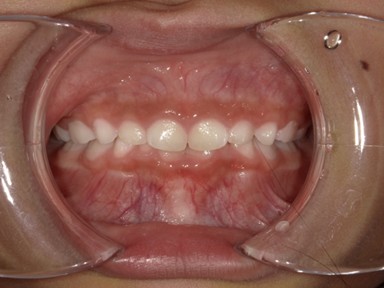

| 主訴 | 生えてきた下の永久歯が曲がっている。これから生えてくる歯も並ぶか心配。 |

| 治療内容 | マイオブレース(J1 → J2 → K3 → T4)と拡大床(BB1)を使用しました。 口腔周囲筋トレーニングも併用しました。 (抜歯:なし、ワイヤー矯正:使用せず) |

| 治療期間 | 78ヶ月(永久歯列完成まで経過観察) ※治療開始から2年間は毎月通院し、その後は3~4か月に1回の頻度で経過観察を継続。 |

| 治療回数 | 38回 |

| 想定されたリスク | 抜歯や全顎ワイヤー矯正のリスクがありました。 |